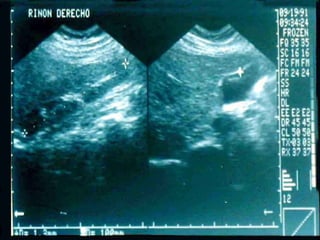

SONOGRAMA ABDOMINAL EVALUACIÓN TAMAÑO ( Hepatitis, I.C.C., Cirosis) FORMA (lobular en cirrosis) LOCALIZACIÓN ( de masas) PATRON SONOGRÁFICO ( hiperecoico gris)

SONOGRAMA ABDOMINAL EVALUACIÓN HIGADO SISTEMA BILIAR BAZO  RIÑONES PANCREAS ( no específico)